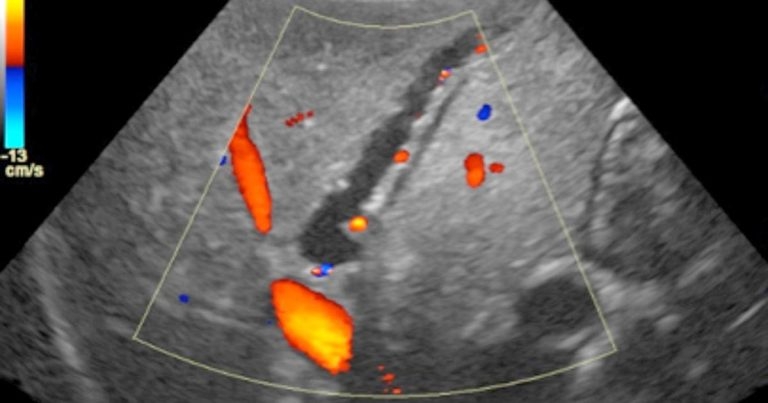

Figure 2 shows a dilated common bile duct (CBD) surrounded by abnormally hyperechoic fat consistent with localised inflammation. The normal diameter of the CBD in the dog is up to 3mm, whereas Smartie’s CBD measures almost 6mm in diameter and is suggestive of secondary extrahepatic biliary obstruction.

A further potential consequence of a mucocele is the development of extrahepatic biliary obstruction. This can occur if abnormal mucinous material migrates into the CBD, and, in such cases, sonographic evidence of intrahepatic and extrahepatic bile duct dilation may exist. Dilated intrahepatic bile ducts may be recognised on ultrasound by the presence of tortuous vessels with hyperechoic walls and variable diameter travelling through the liver parenchyma. Unlike blood vessels, no evidence will be found of flow within bile ducts when interrogated with colour Doppler. When multiple intrahepatic bile ducts are dilated, this is sometimes referred to as the “too many tubes” sign (Figure 4).